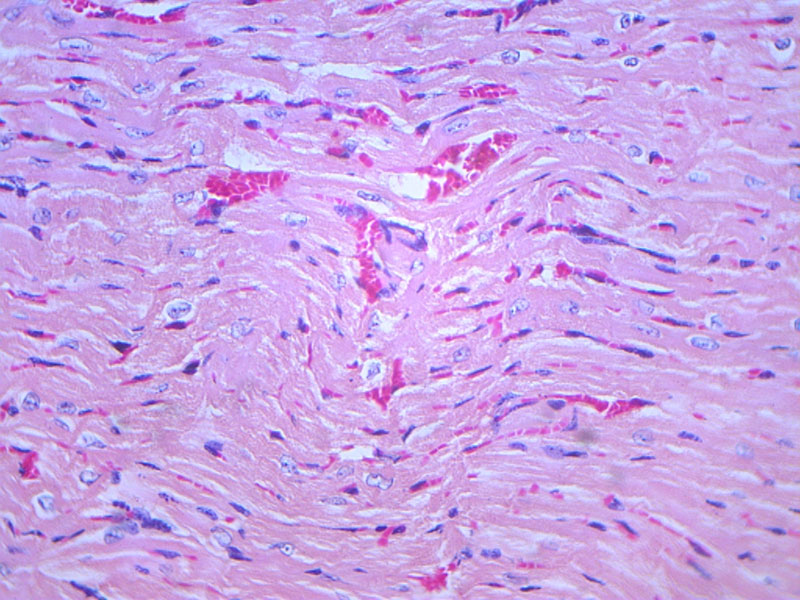

特別是動(dòng)物死亡或新鮮組織離體后,極易發(fā)生組織自溶或細(xì)菌感染,...